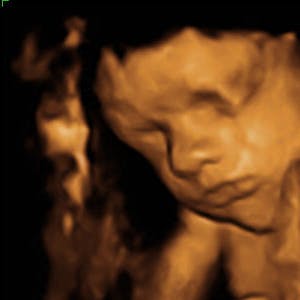

Gravid

Vi gør en dyd ud af at klæde dig godt på både før, under og efter din graviditet. Vi ved, at der kan komme mange spørgsmål til din graviditet, fødsel, amning, din babys udvikling og mange flere emner, derfor har vi samlet guides, tips & tricks samt læsernes egne fortællinger i dette gravid univers.